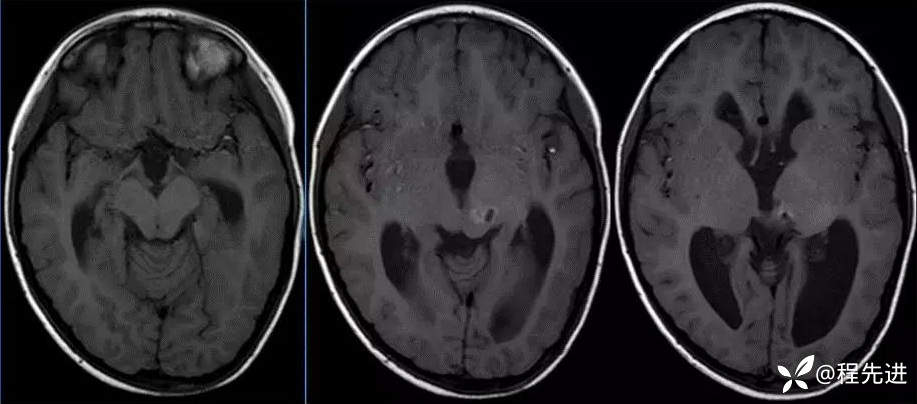

MR